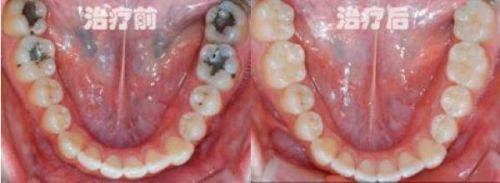

补牙:针对龋坏牙齿进行填充修复,修复牙齿完整性。